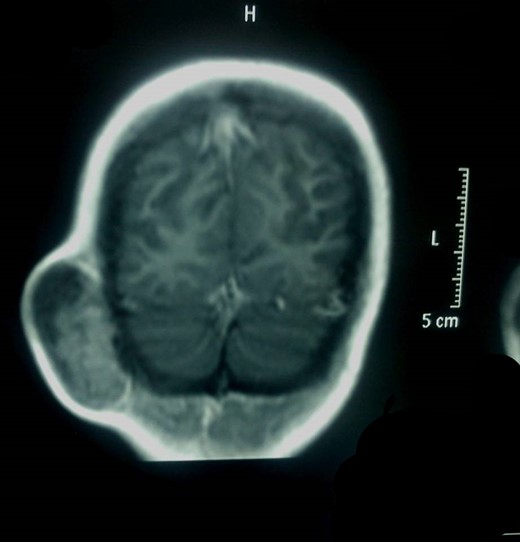

MRI showed an encapsulated spindle formation in the region of the soft tissues of the right suboccipital region (Fig. 4). It was primarily located in the subcutaneous tissues, with a broad attachment to the outer table of the diploe, which appears to be thinned. It had mainly intermediate signal on T1W and T2W images, combined with some areas of high signal on T2 and low signal on T1. After the intravenous injection of the contrast, it showed inhomogeneous uptake.